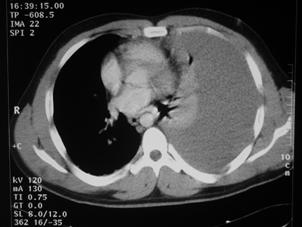

Corp ascutit penetrat in regiunea precordiala Mediastin largit

Aortograma Mediastin largit

Leziune la nivelul istmului aortic

Aortograma.Leziune

situata distal de Aorta

clampata

emergenta arterei subclavii stangi Segment

lezat excizat